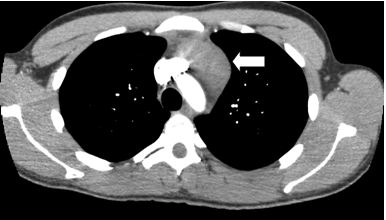

An abnormality was noted in the left mediastinum which prompted his physician to order a computed tomography (CT) of the chest and to refer him to a pulmonary specialist. This CT scan (Figures 2 and 3) revealed a rounded, well-demarcated mass in the superoanterior mediastinal compartment. The largest diameter measured 6.8 x 4.8cm.

Figure 2. Computed tomography (CT) image of the chest demonstrating well-demarcated soft tissue mass in superoanterior mediastinal mass (arrow).